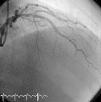

Tratamiento del ángor. Criterios de respuesta. Seguimiento de la respuesta